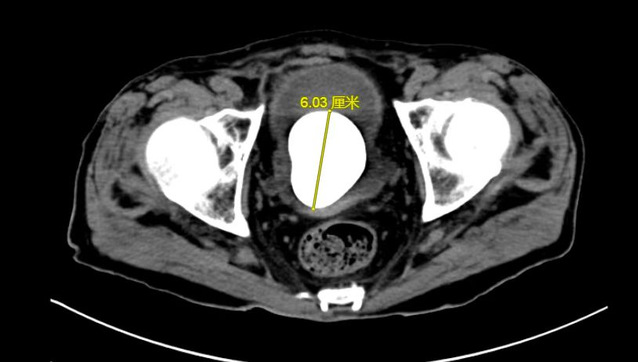

数月来,徐老伯常有尿频尿痛症状,由于近期症状明显加重,甚至出现反胃、食欲不振致使精神萎靡的情况,在当地医院就诊时,被查出膀胱内有一枚6cm*5cm大小的膀胱结石。

目前,治疗膀胱结石的主流手段为经尿道钬激光碎石术,但考虑到患者高龄,且营养状态虽较前好转,但仍较正常老年患者不足,若采取经尿道手术治疗患者“鹅蛋”大小的膀胱结石,患者难以耐受3小时甚至更长时间的手术及麻醉过程,因此,在与患者沟通后,陈建春团队选择了传统的膀胱切开取石术。最终,在手术麻醉、ICU及护理团队的共同协作下,陈建春主任团队顺利将“鹅蛋”大小的膀胱结石自患者体内取出,整个手术过程仅用30分钟。